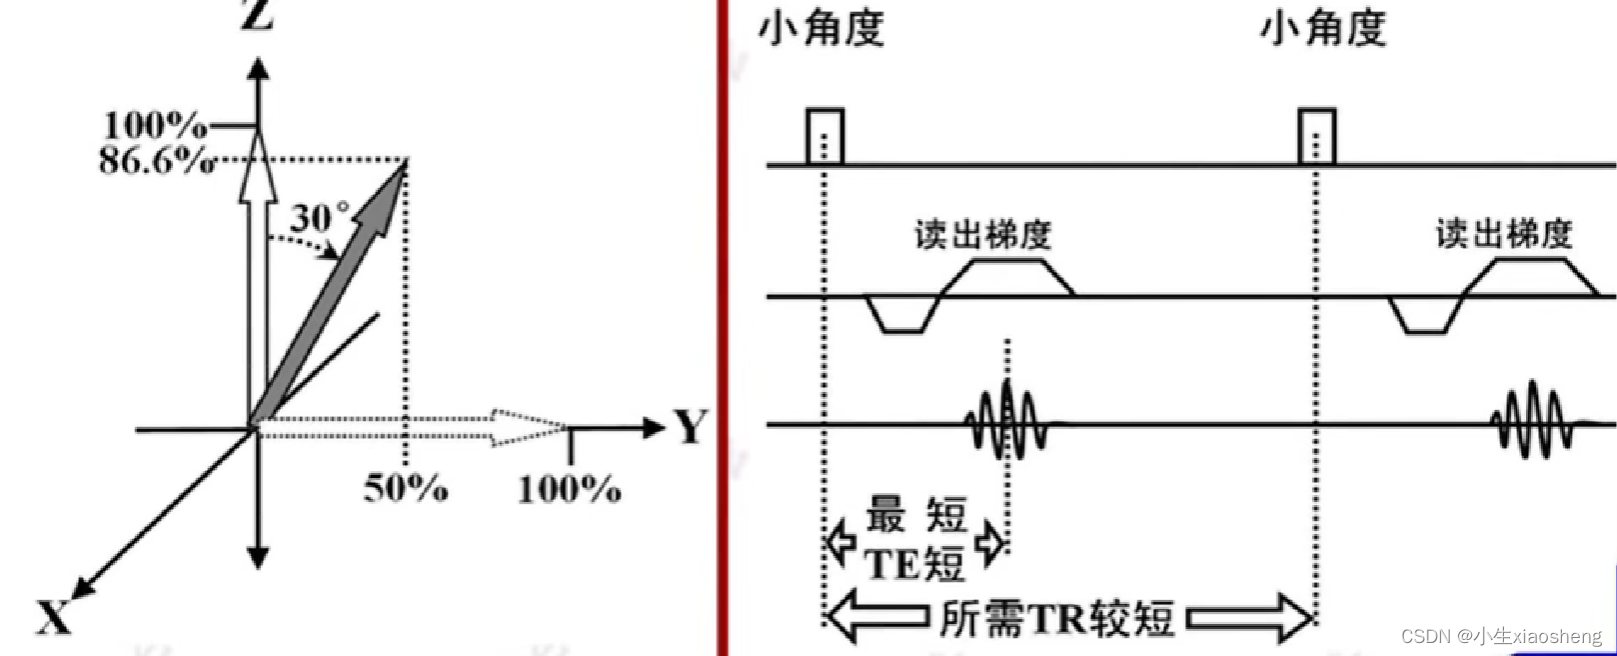

五、梯度回波类序列

GRE就是梯度回波